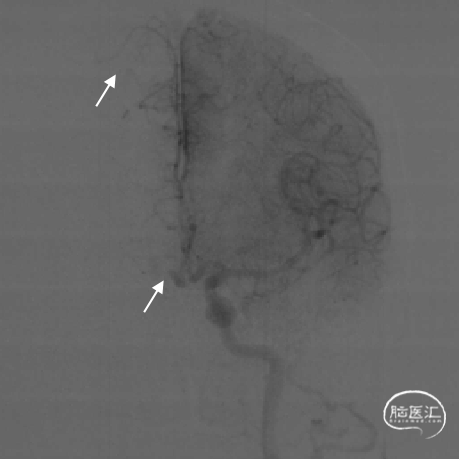

DSA评估:右侧颈内动脉末端闭塞,颈内动脉走行迂曲

DSA评估:前交通开放,左侧颈内动脉通过前交通动脉向右侧大脑前动脉代偿供血,并逆向充盈至右侧大脑前动脉A1段

DSA评估:后循环未见明显向右侧颈内动脉供血区代偿供血

DSA提示右侧颈内动脉末端闭塞,局部可见“杯口”征;左侧颈内动脉通过前交通代偿,并逆向充盈至右侧A1段;该患者为颈内动脉末端“T”型闭塞。结合房颤病史,病因分型为心源性栓塞。